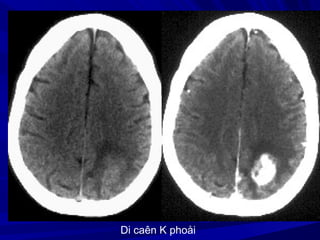

Di caên K phoåi

Di caên Kphoåi